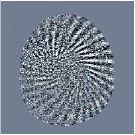

V-B Visualising MRFResnet segments on Bloch manifold

Remark 1.

Continuity of implies that adjacent segments correspond to distinct . Indeed, if and the only difference is in the offsets , then won’t intersect on boundaries. Therefore they are not adjacent segments unless contradicting the continuity assumption.

This remark gives an idea for visualizing the input space segments. For densely sampled input signals , we compute derivatives of the weighted outputs (15) with respect to inputs using back propagation. These will determine the input-dependant slopes in the affine spline formulation (16) i.e. rows of at a point are populated as follows :

| (17) |

By vector quantisation (e.g. k-means clustering) we cluster regions of that output distinct slopes and identify the segments . Similar routine could apply to compute input space partitions by clustering back-propagated output derivates after each residual block (Theorem 1 and Remark 1 also hold for the intermediate blocks of ).

According to [44] as we progress into deeper layers, partitions will be subdivided into smaller segments in a hierarchal fashion. This can be observed in Figure 2 where we adopted the above routine for the T1/T2 encoding MRF sequence used in our experiments and visualised multi-scale (from coarse-to-fine) partitions obtained after each residual layer. The Bloch response manifold is sampled across fine-gridded T1/T2 values (i.e. MRF dictionary) to visualise the intersection of the input space segments with this manifold (results are visualised across the three dominant principal component axes). MRFResnet encoder learns about a thousand partitions for its end-to-end mapping . In the light of (16) we know that for each partition the network implicitly encodes deep matched-filters (the rows of or alternatively ) and an offset term to locally linearly regress the T1/T2 outputs in that segment. As such instead of memorising 100K dictionary atoms used for training, the network learns a compact piece-wise affine approximation to the Bloch manifold projection (5) as a rapid and memory-efficient alternative to DM’s point-wise approximation (7). The total number of parameters used by the MRFResnet (Table I) are two hundreds times less than the size of the dimension-reduced MRF dictionary. Figure 3 shows the Bloch responses for a range of T1/T2 values, as well as deep matched-filters learned by MRFResnet to predict each of these quantities in this range from noisy inputs. Computed through (17), match-filters are one-dimensional analogues of the saliency maps a.k.a. deep dream images [49], measuring sensitivities of the T1/T2 output neurons with respect to the inputs.